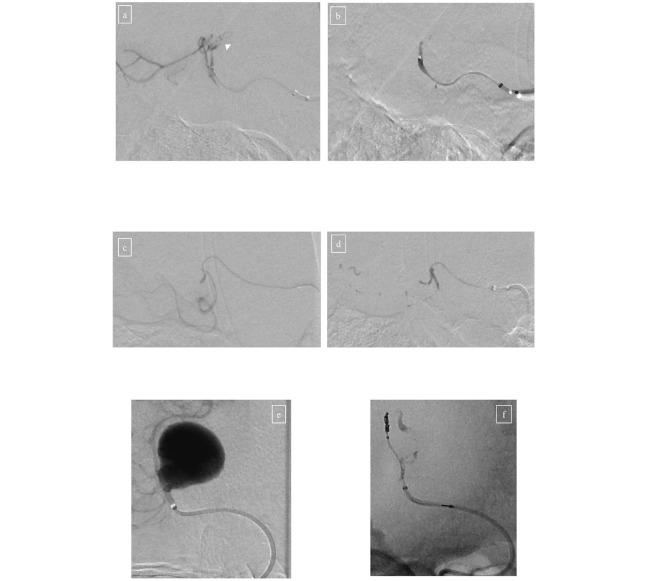

We describe a case of internal trapping including the vasa vasorum for a thrombosed giant rapidly growing posterior cerebral artery aneurysm and performing a detailed analysis. A 48-year-old woman was followed up in our hospital for a thrombosed large posterior cerebral artery aneurysm located in the P2 segment. She initially presented after experiencing a sudden headache on two occasions. Head computed tomography and magnetic resonance imaging indicated a larger aneurysm than before. Digital subtraction angiography with balloon occlusion test was assessed, and internal trapping was sequentially conducted. We detected that the vasa vasorum originated from the posterior temporal artery. Therefore, we embolized the posterior temporal artery including the vasa vasorum using -butyl-2-cyanoacrylate and Lipiodol. Next, the anterior temporal artery was embolized with -butyl-2-cyanoacrylate and Lipiodol, posterior temporal artery P3 segment and the aneurysm and finally the proximal P2 segment were embolized with coils. Final vertebral and internal carotid angiography showed complete obliteration of the aneurysm. On the day after the procedure her paresis worsened and she developed left upper quadrantanopia, however was finally discharged with no hemiparesis. We reported a case of a rapidly growing thrombosed giant posterior cerebral artery aneurysm treated by parent artery occlusion including the vasa vasorum with detailed image analysis.